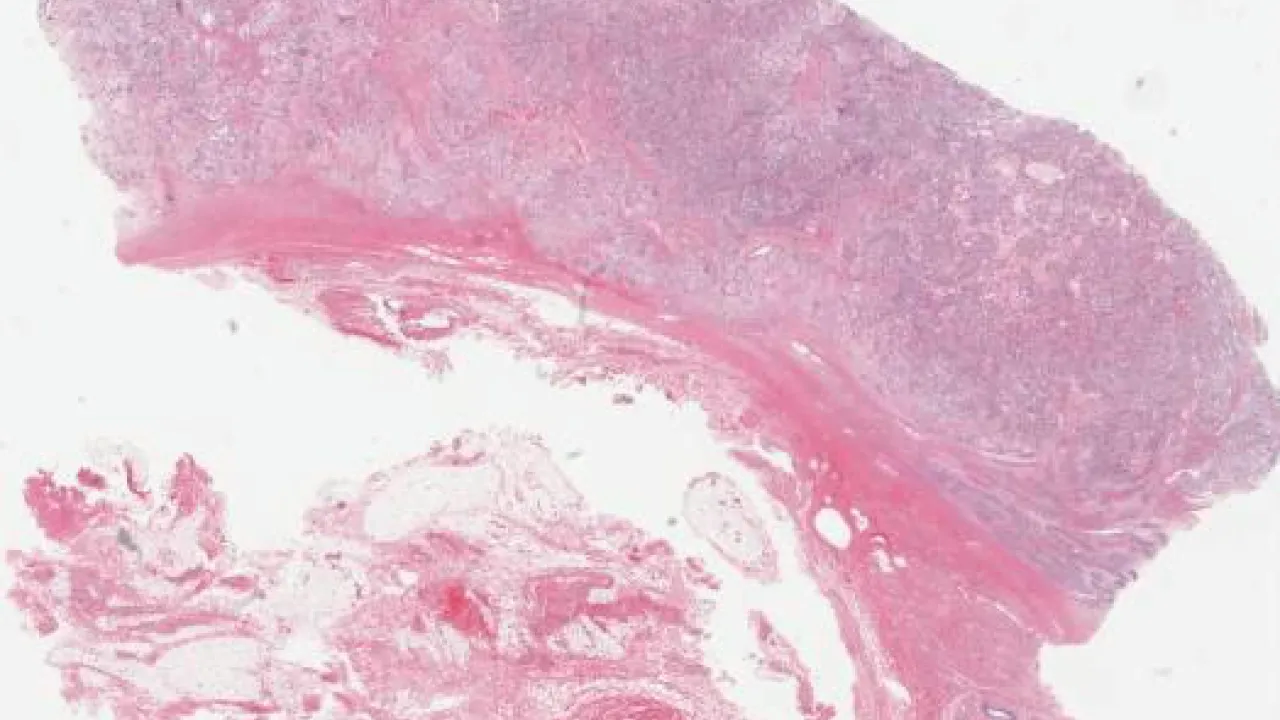

Lower Urinary Tract and Male Genital System

Subscribe to Lower Urinary Tract and Male Genital System